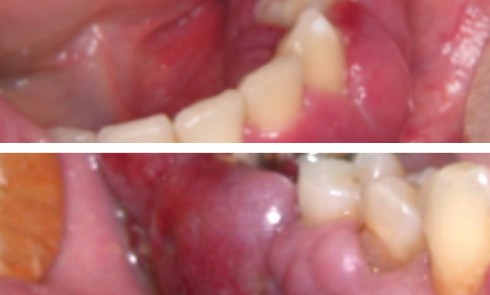

Article réservé à nos abonnés Encore des épulis ?

CAS 1 Motif de la consultation. Patient de 51 ans qui est venu consulter car il avait découvert une tumeur...